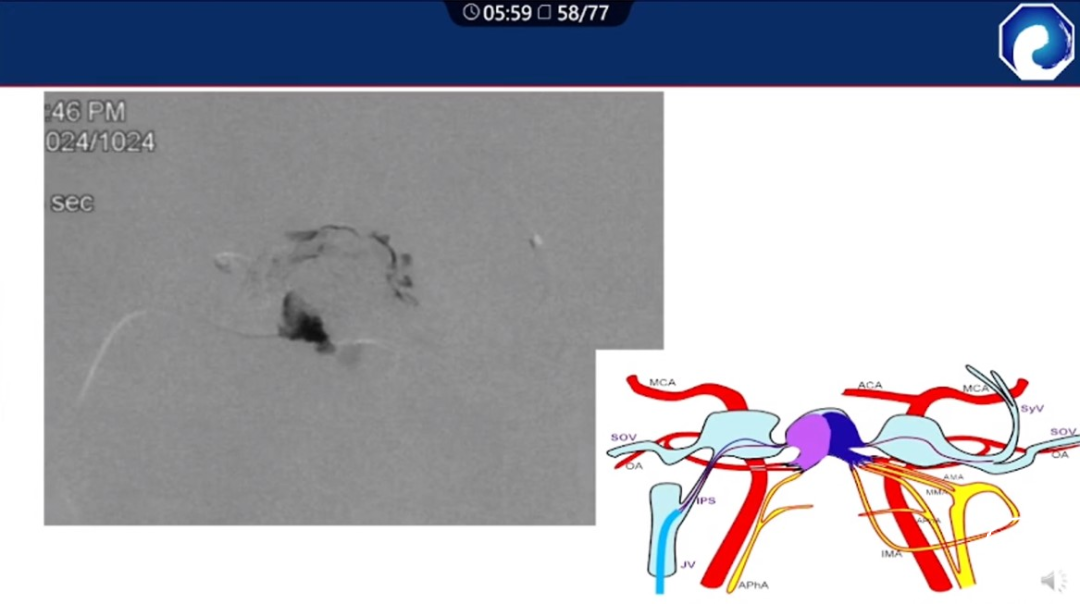

痿口静脉端的识别至关重要。

痿口静脉端精准完全闭塞是DAVF治愈的关键。

靶向性栓塞可以减少海绵窦分隔的过渡栓塞,有利于减少颅神经并发症,恢复海绵窦的正常引流功能。